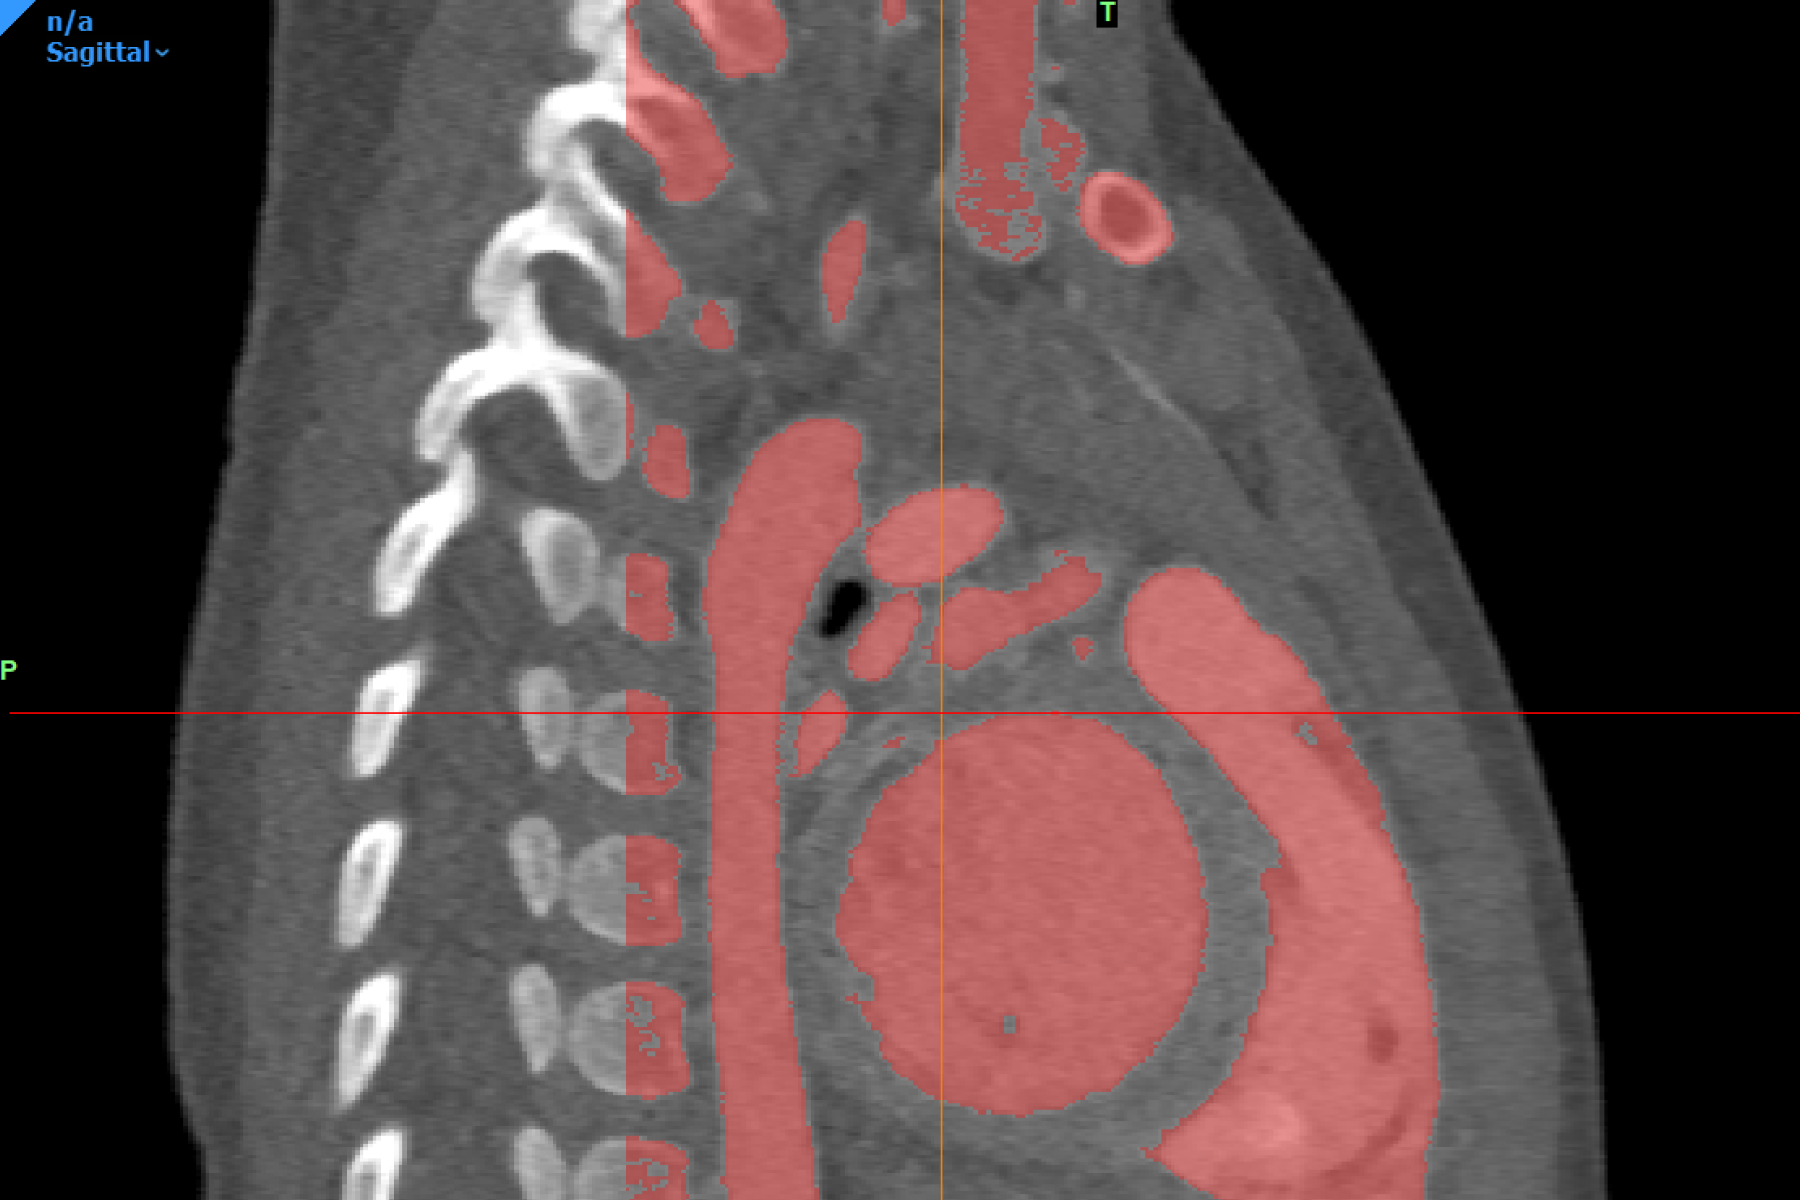

To develop this surgical training tool, the Digital Lab utilized established 3D modeling protocols. The virtual 3D model of the heart was developed with the abnormal anatomical features observed in patients with atrial septostomy, notably, the transposition of the great arteries which impacts the proper flow of oxygenated blood. The model was developed in consultation with a pediatric cardiologist using contrast-enhanced computed tomography scans obtained from infants with this condition. After the virtual model was approved, a physical model was fabricated following standard procedures established by the Digital Lab.

To ensure that the 3D printed heart was able to effectively replicate the elasticity and texture of cardiac tissue and provide a realistic experience to users, flexible and rubber-like materials were utilized during the printing process. Extended blood vessels were included to replicate the access points used by surgeons completing this procedure. A 5mm hole was created in the atrial septum to simulate the atrial septal defect (ASD). This 3D printed heart was then suspended within a simulator developed using Computer-Aided Design (CAD) software. This simulator provides access points that accommodate training for different procedural approaches to ensure that the model is generalizable.